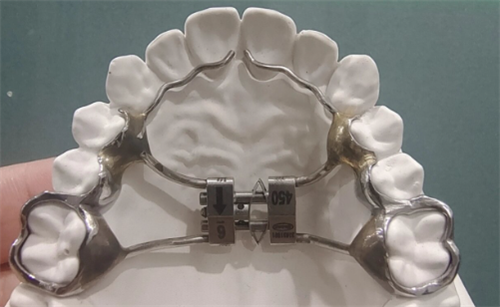

固定式扩弓器价格范围:5000元至15000元(一副)

固定式扩弓器:高端固定式扩弓器价格可达10000元以上(一副),通常采用优质材料和精细制作工艺,适合牙齿畸形程度较重或对矫正结果有较高要求的患者。